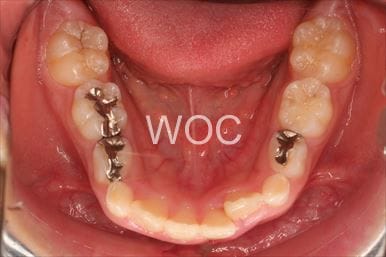

叢生

治療前1

治療前2

治療前3

治療前4

治療前5

- 年齢:8歳2ヶ月

- 主訴:ガタガタ

- 診断名:叢生、上顎前突、過蓋咬合

- 装置:機能的矯正装置

- 期間:6年5ヶ月 ※

- 費用:基本矯正料金:350,000円